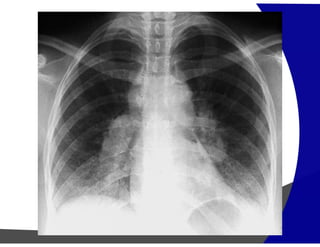

Fibrose Pulmonar

Achados por Imagem

• Raio – X – geralmente normal

Avançada – redução volumétrica e opacidade reticulares

subpleurais com gradiente de apresentação ápico-basais.

• TCAR

Redução volumétrica

Opacidades reticulares subpleurais

Faveolamento (macro)

Bronquiectasias de tração

Gradiente de envolvimento apico-basal

Heterogenicidade espacial e temporal de distribuição